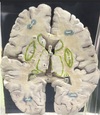

1. At what level through the cerebrum is this section taken? 2. Identify the specific structure labelled 1. 3. Identify the structure labelled 2. 4. Identify the structure labelled 5. 5. Identify the specific structure labelled 8. 6. Identify the structure labelled 10.

1. The level of interventricular foramen 2. Genu of Corpus Callosum 3. Septum Pellucidum 4. Column of Fornix 5. Spleenium of Corpus callosum 6 Crus of Fornix

56

1. Identify the specific structure labelled 3. 2. Identify one afferent fiber of this structure. 3. Identify one efferent fiber of this structure.

Caudate Nucleus Cortico striate, thalamo striate, nigro striate , Striato pallidal , Striato nigral

57

1. Identify the specific space labelled 4 2. Give its developmental origin.

Anterior horn of lateral Ventricle Central Canal of neural tube

58

1. Identify the structure labelled 6.

thalamus

59

1. Identify the structure labelled 7. 2. Give its subdivisions. 3. Give its afferent fibers. 4. Give its efferent fibers.

1. Lentiform Nucleus 2. Putamen, globus pallidus externas, globus pallidus internus 3. Corticostriatal, nigrastriatal 4. striatonigral, striatalpallidal

60

1. Identify the structure labelled 9. 2. Identify the structure labelled 11. 3. Identify the vessels lining the structure labelled 11.

1. Tail of caudate nucleus (goes to amygdala) 2. Insular cortex 3. short perforator branches from the superior division of the middle cerebral artery (MCA)

61

1. Identify the structure labelled 12 2. What type of meninges covers this structure? 3. What is the main function of this structure? 4. In which ventricular structures is this structure present? 5. In which ventricular structures is this structure absent?

1. Choroid Plexus 2. Pia Mater 3. Produces SF in ventricles of brain 4. Lateral 5. cerebral aqueduct, frontal horn of the lateral ventricle, [1] and occipital horn of the lateral ventricle

62

1. Identify the specific structure labelled 13. 2. What fibers can be found in this structure?

1. Posterior Limb of Internal Capsule 2. Corticospinal Fibres

63

1. Identify the specific structure labelled 14. 2. What fibers can be found in this structure?

1. Anterior Limb of internal capsule 2. Frontopontine, thalamocortical